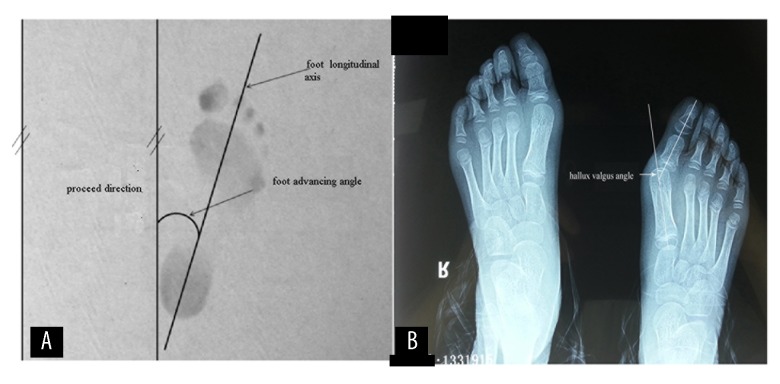

All of the patients were provided with a 1-year treatment, including some children who improved after 6 months of treatment. Patients were assessed at the orthopedic clinic by a local doctor in general practice every 6 months; foot progression angle and presence of and degree of hallux valgus angle were measured when walking barefoot (Figure 1A, 1B). Patients’ feelings were also recorded. Cases of hallux valgus were assessed over a further 24-month period following cessation of treatment. Foot progression angle was defined as the angle between the longitudinal axis of the foot and the direction of travel [12]. We measured the hallux valgus angle by radiographic work-up while weight-bearing, and the hallux valgus angle was defined as the angle between the longitudinal axis of the first metatarsal and first proximal phalanx. The diagnostic criterion used to assess the degree of hallux valgus was the presence of hallux valgus angle greater than 20° [13]. The foot progression angle and hallux valgus angle were recorded as mean ± the standard deviation (SD). A two-way t test was used to compare changes in foot progression and hallux valgus angles, and the recovery rate of the 2 groups was tested by the chi-square test; statistical significance was set as P≤0.05.

Figure 1.

Schematic diagram of foot progression angle (A) and hallux valgus angle (B), showing how these values are measured.